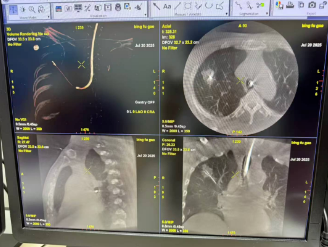

术中

手术在全麻气管插管下顺利完成。术中,在EBUS精确定位下,团队将冷冻探头精准置入右肺上叶尖段及前段支气管壁的新生病灶。分区域对两处肿瘤分别进行了4个循环的精确冷冻消融,使肿瘤组织充分凝固坏死。术程顺利,未出现明显出血或气胸,患者生命体征平稳。